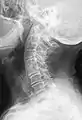

Several congenital block vertebrae in the transition from the thoracic to the lumbar spine and hemivertebrae.